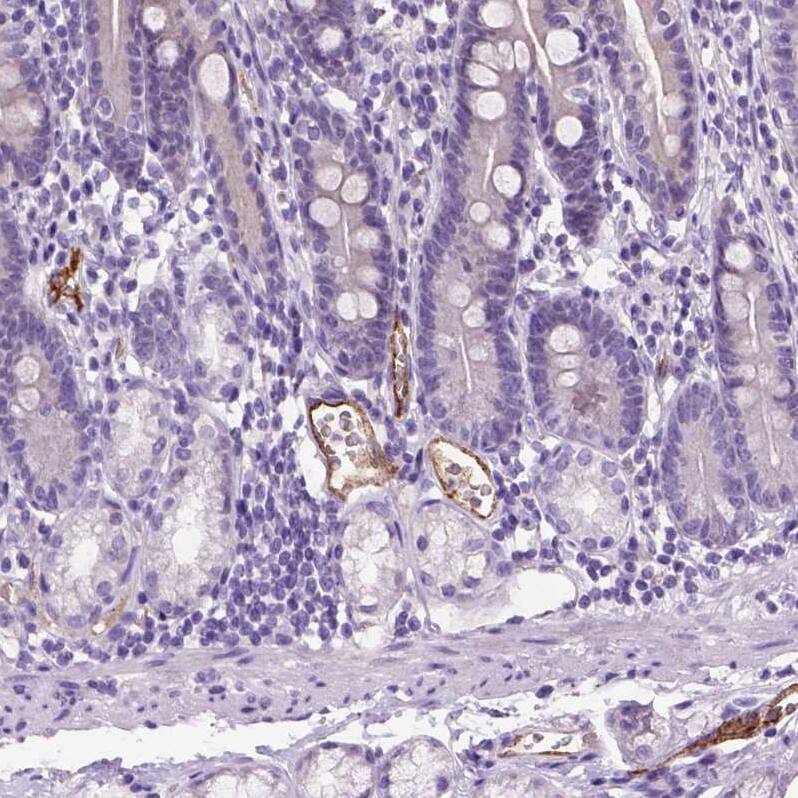

Staining of human duodenum shows moderate cytoplasmic positivity in endothelial cells.